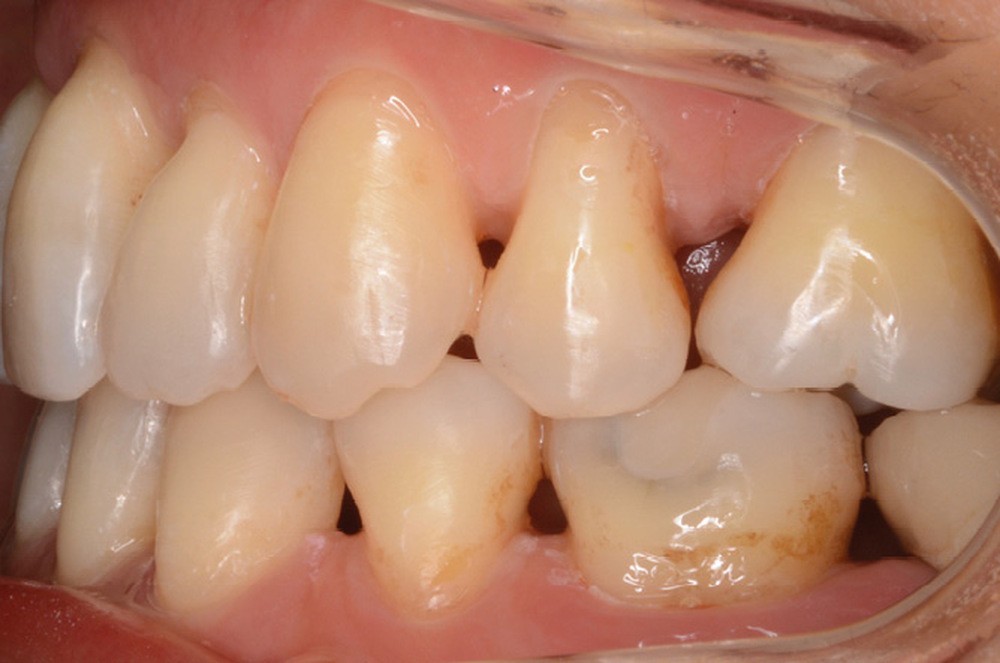

Une contention collée de 13 à 23 et de 33 à 43 (chaînette en alliage précieux Ortho-flextech), ainsi qu’une gouttière thermoformée maxillaire sont mises en place. Le suivi parodontal est trimestriel.

Notre traitement a permis de répondre à la demande de la patiente [3] en réduisant la compression articulaire dont elle souffrait, atténuant par la même occasion ses symptômes, tout en améliorant nettement son pronostic parodontal et dentaire sur le long terme. Mme J. est très satisfaite du résultat obtenu.